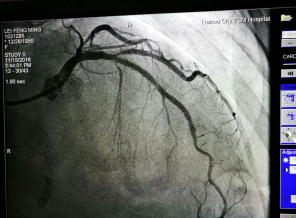

???我院成功開展市屬醫(yī)院首例冠狀動(dòng)脈內(nèi)膜旋磨術(shù)???? 在心臟血管內(nèi)開“隧道”,用高速旋轉(zhuǎn)的鉆石磨頭將堵塞心臟血管的鈣化斑塊磨碎,以此打通血管進(jìn)行冠心病的介入治療,這看起來像科幻電影里的場面,在我院實(shí)現(xiàn)。近日,我院完成了全市市屬醫(yī)院首例冠狀動(dòng)脈內(nèi)膜旋磨手術(shù),成功開通了血管,解除了患者長期存在的胸悶...